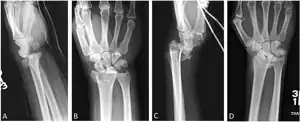

Additional images

-

Lateral projectional radiograph of the same fracture -

Barton's and reverse Barton's